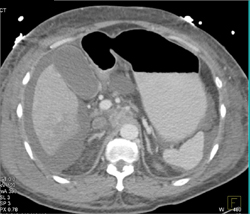

Ulceration of the Aortic Arch